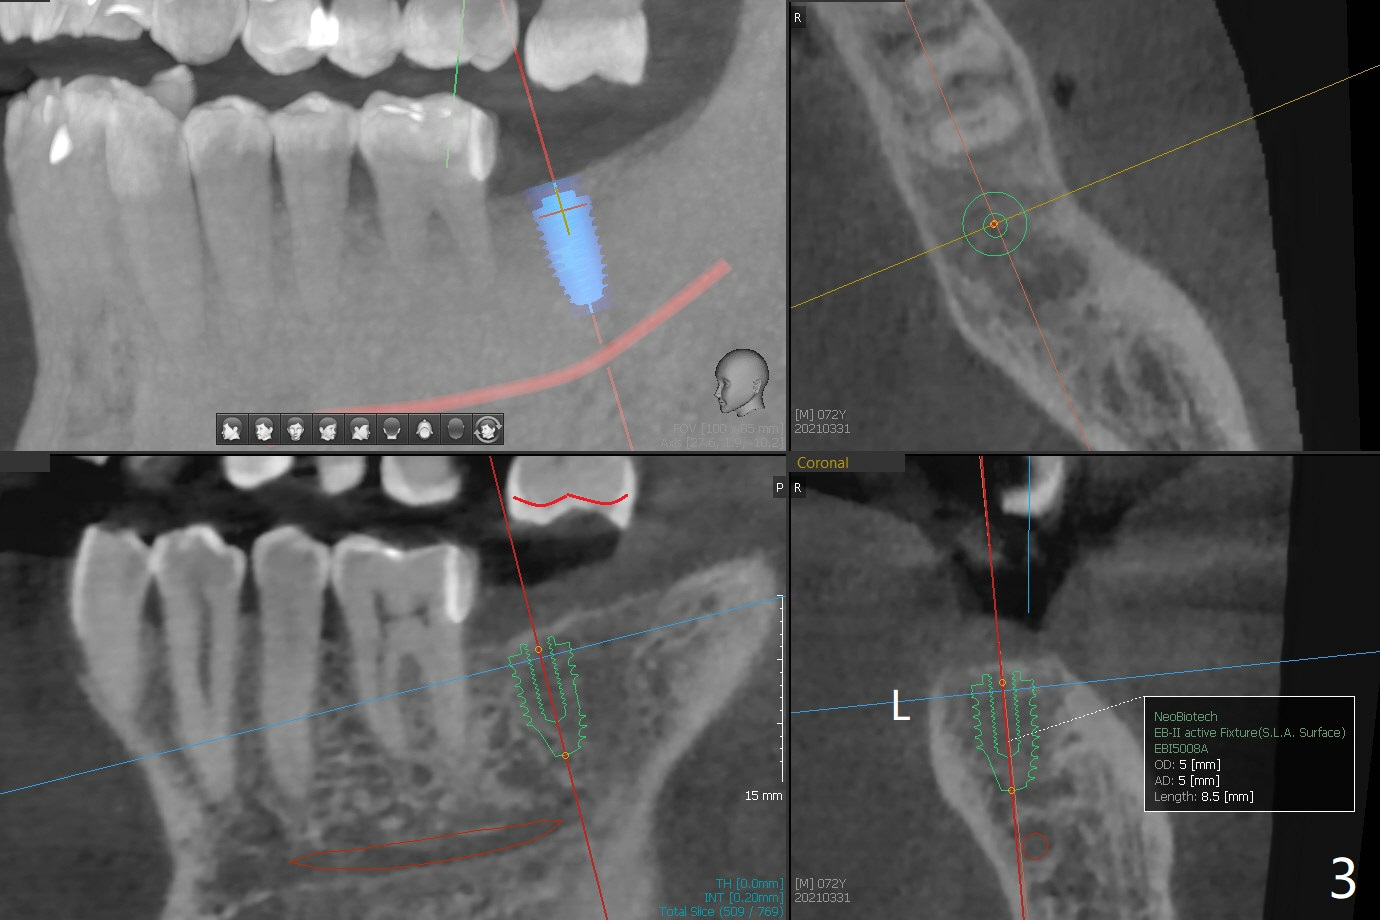

A 72-year-old man agrees to have #14 to be extracted for implant (Fig.1). In the first stage, impression is taken for #14 and 18 implant placement with guide. Due to odontogenic sinus infection (Fig.1,2 *), Z pack will be taken to prevent implant infection associated with sinus lift (Fig.2). Remove provisional and abutment once the sockets heal. To combat #15 supraeruption, the implant at #18 will be placed deep; if the torque is high, place a large diameter healing abutment or provisional with large base will be fabricated so that a short cuffed abutment will be used for final restoration. Heavy occlusal reduction at #15 will be conducted (Fig.3 curved lines). In spite of the fact that the bone height at #3 is 3-4 mm, the sinus floor is flat (Fig.4). Internal sinus lift is not expected to be too difficult. Use Magic Sinus Lifter, followed by implant placement at the same stage (Fig.5,6).